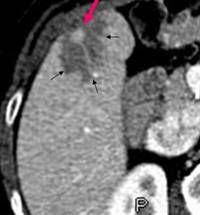

Une stéatose focalisée périlésionnelle est classiquement retrouvée dans les métastases hépatiques des insulinomes malins (1-4). Cette stéatose pourrait être secondaire à l’élévation de l’insulinémie qui, lorsqu’elle est prolongée, inhibe l’oxydation des acides gras libres et stimule leur estérification en triglycérides. Ces derniers s’accumulent alors dans les hépatocytes et génèrent ainsi une stéatose. Plus rarement a été décrite la possibilité d’une stéatose pancréatique périlésionnelle dans les insulinomes (2, 5). Le mécanisme physiopathologique de cette stéatose pancréatique est probablement le même qu’au niveau hépatique. La possibilité d’une ischémie péritumorale potentiellement responsable de modifications de la composition en graisse du tissu sain péritumoral ne peut cependant être exclue (5). Des lésions de stéatose péri lésionnelle ont également été décrites dans des glucagonomes (4). Une élévation prolongée du glucagon pourrait être responsable d’une augmentation de la lipolyse dans les hépatocytes avec apparition d’une stéatose périlésionnelle. En conclusion, la mise en évidence d’une stéatose périlésionnelle hépatique ou pancréatique pourrait faire évoquer le diagnostic d’insulinome ou plus rarement de glucagonome.

Insulinome (Flèche rouge) Stéatose (flèches noires)